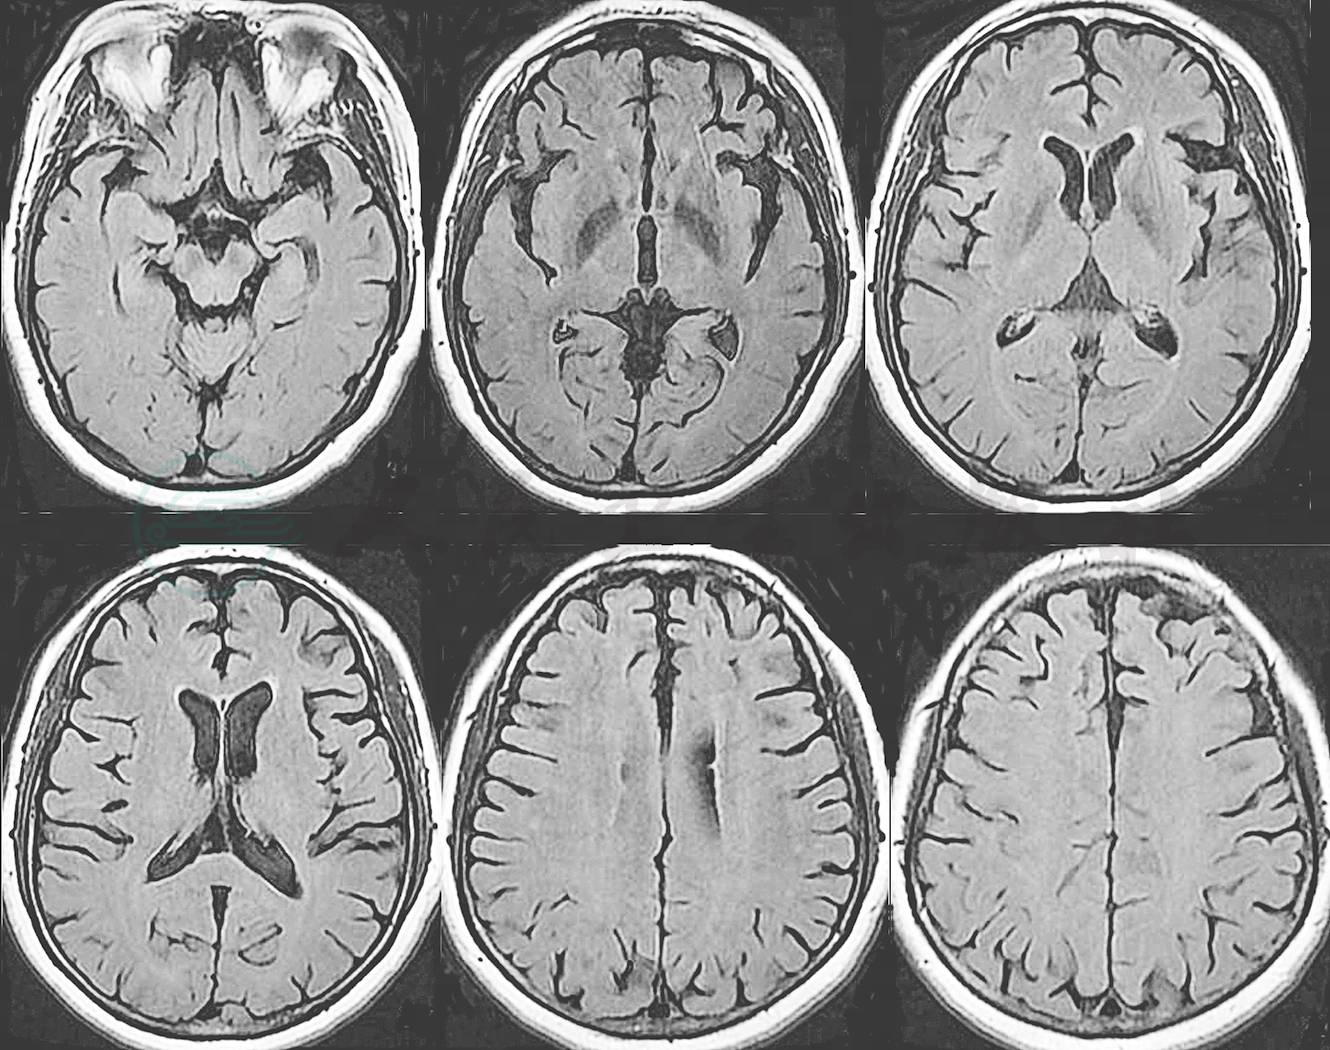

头颅MRI显示脑白质脱髓鞘变性,颞叶前部和额叶稍显萎缩,左侧为著(图1)。

图1 患者头颅MRI表现

.进一步分析病史:H女士在疾病早期主要表现淡漠和人格改变,逐渐出现言语交流的困难,明显的社交不适切行为,存在刻板行为以及食欲和进食行为的改变,认知功能方面以言语/语言功能与执行功能损害为主,情景记忆损害不突出,视空间功能相对保留,结合头颅MRI结果,诊断为额颞叶痴呆。治疗上逐渐减停奥氮平和米氮平,保留度洛西汀,合并美金刚10mg/d。调整药物治疗期间,H女士情况稍有好转,情绪变得稳定,反复上厕所次数明显减少,言语交流较前稍显顺畅,有时主动诉说一些简单需求,主动要求和病友玩麻将。同时给予家属支持,对家属进行疾病知识及照护技巧培训,相关风险(如脱抑制行为可能引发的社交危机等)防范,以及非药物干预的方法和可利用的资源。

综上,考虑H女士为bvFTD的可能性最大。在FTD的诊断和鉴别诊断中,影像学起到至关重要的作用。结构MRI和CT的特征性表现为额叶或颞叶前部的显著萎缩,额岛区域的萎缩尤其提示FTD。FDG-PET和SPECT显示这些区域的低代谢和低灌注。tau-PET是非常有前景的影像学检查手段,有助于早期识别以tau病理为主的FTD。淀粉样蛋白PET成像有助于与AD的鉴别。